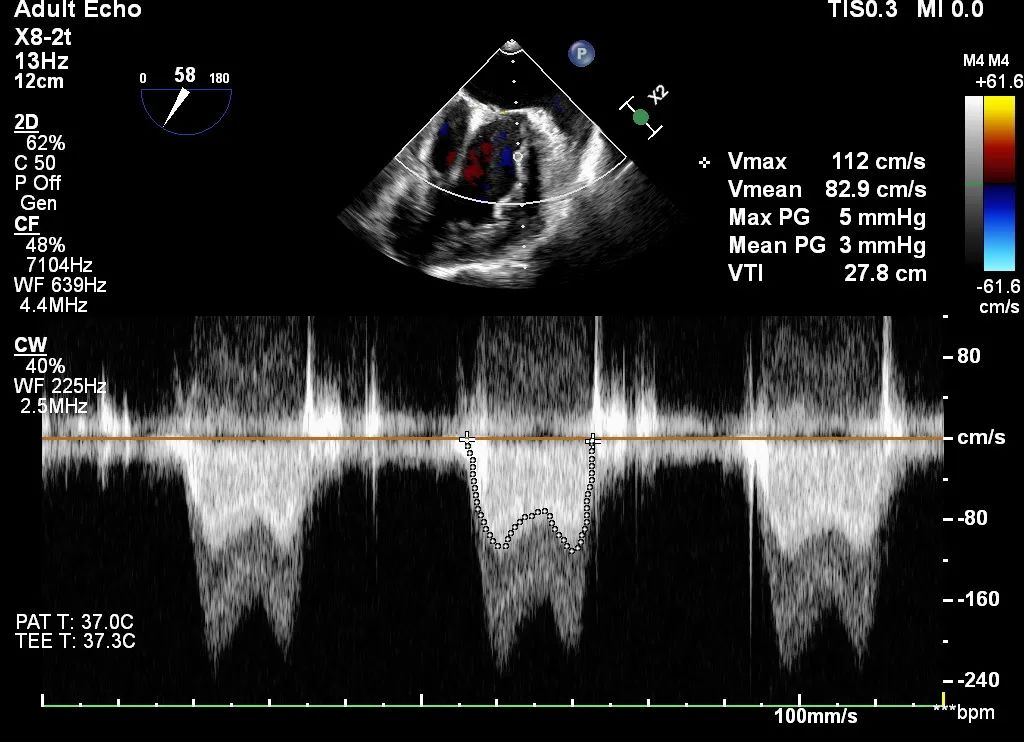

术后平均跨瓣压差3mmHg

全麻后,首先在心前区的肋间切开3-4CM小切口,暴露心脏的心尖位置,心尖穿刺后进入导丝,利用导丝交换导管鞘完成通路建立。将系统送入左心房,顺利到达二尖瓣病变区域。在经食道超声引导下,术者通过反复评估二尖瓣反流位置、抓捕位置、反流程度,在2区主动脉瓣与二尖瓣闭合线垂直进行巧妙夹合,最终植入一枚ValveClamp®MVC-Ⅲf夹。超声评估夹子固定良好,组织桥完整,无葫芦征,位置、轴向均符合预期。患者术后反流程度从大量转至少量,手术取得圆满成功。患者恢复良好,已经顺利出院。